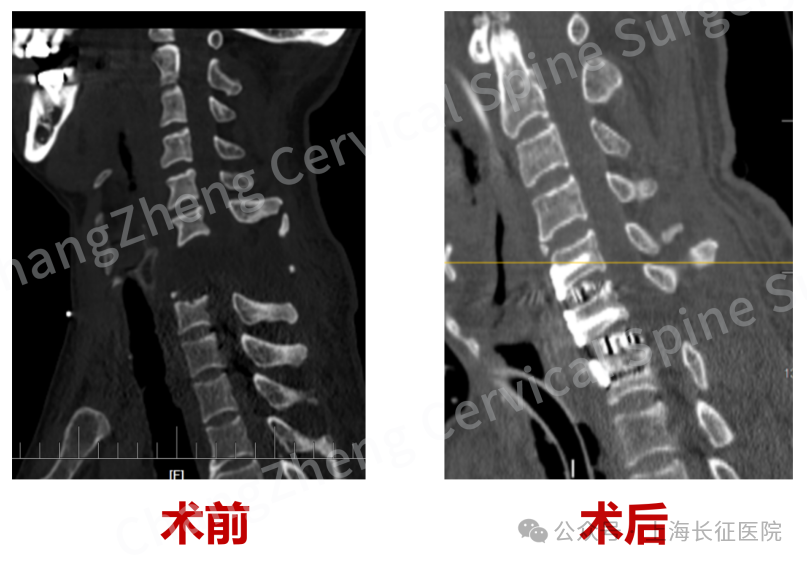

术前、术后影像对比,手术效果良好